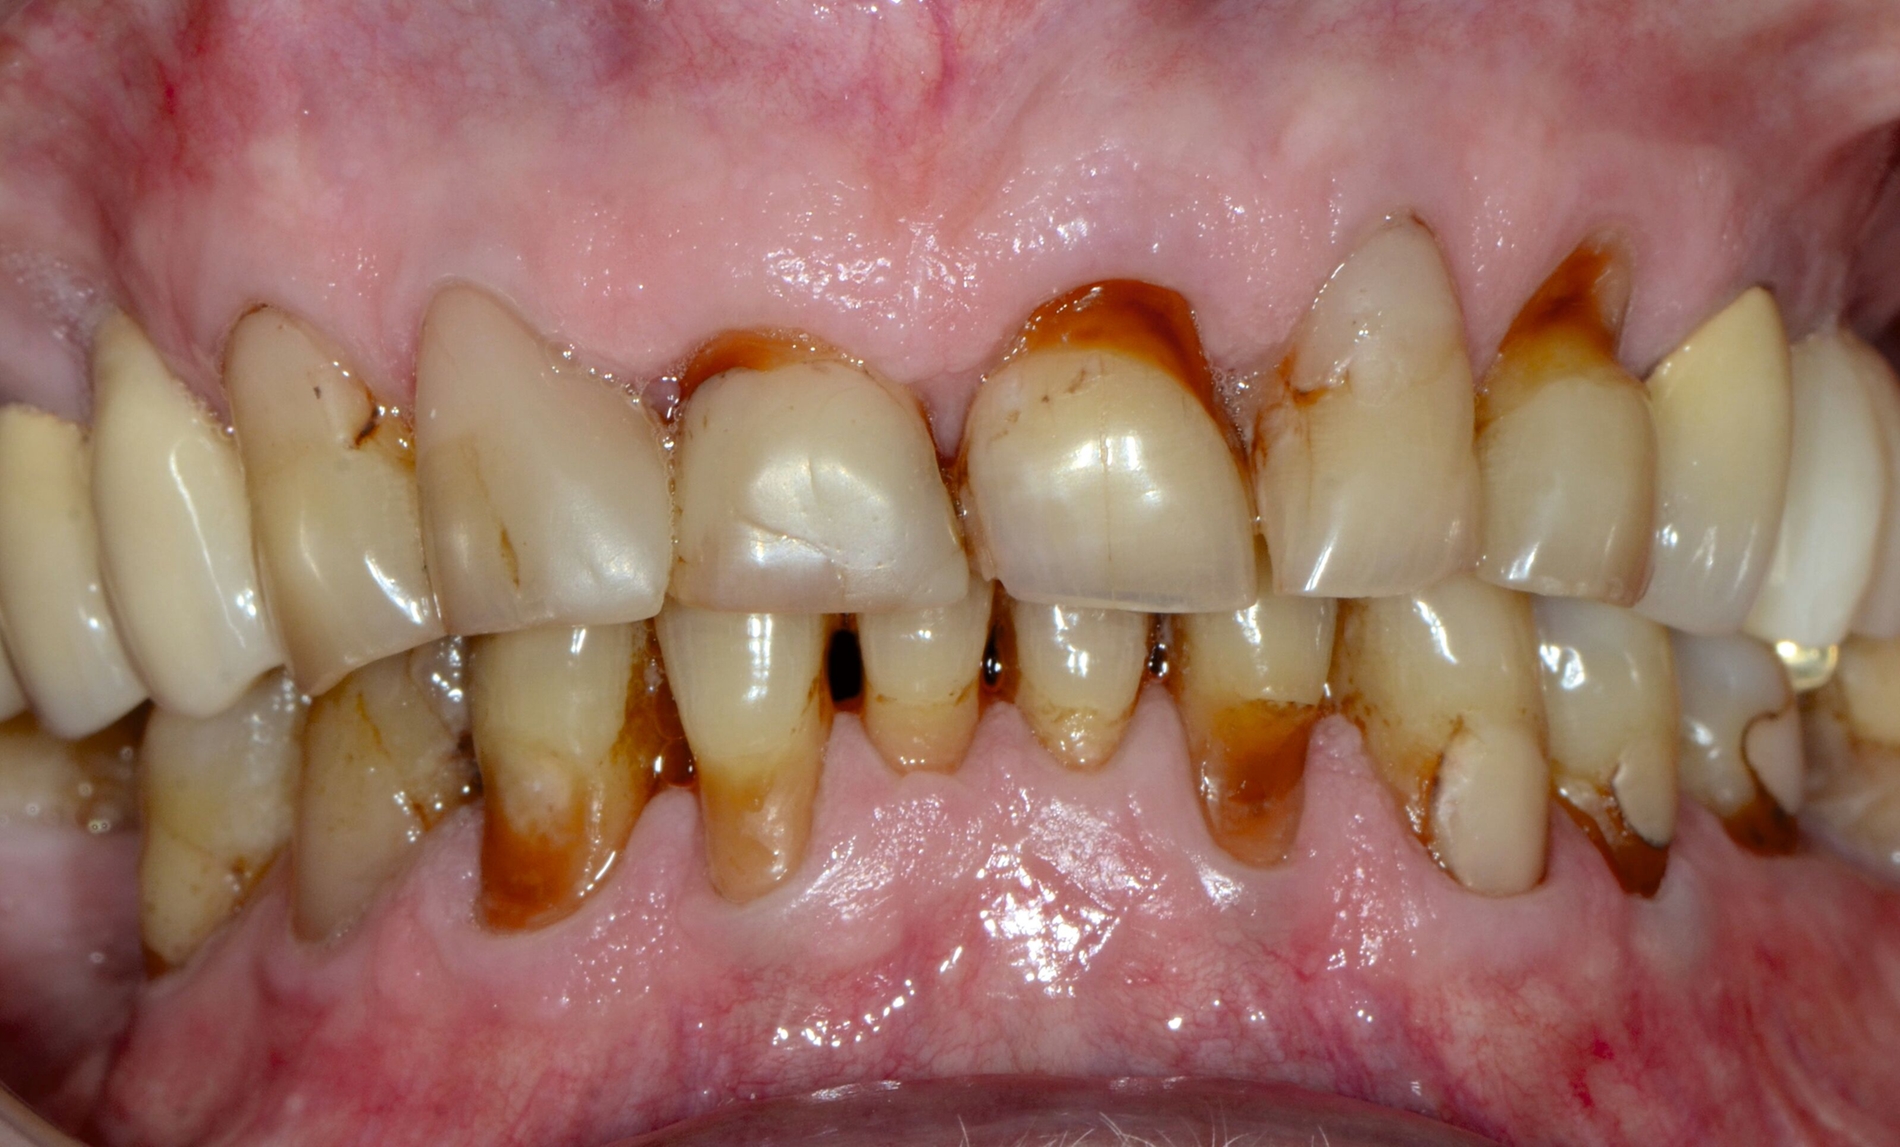

... für Zahnformkorrekturen im Frontzahnbereich

Ähnliche Ergebnisse wurden bei Zahnformkorrekturen erzielt. Die untersuchten Studien berichteten über hohe bis sehr hohe Überlebensraten von Komposit-Restaurationen mit Nachbeobachtungen bis zu 15 Jahren. Beim Vergleich mit indirekten Keramikveneers zeigten diese zwar höhere Überlebensraten, doch basiert diese Schlussfolgerung auf einer einzelnen Studie mit kurzer Nachbeobachtungszeit [Meijering et al., 1998]. Die Nutzen-Schaden-Bewertung spricht klar für den Einsatz von Kompositen zur Zahnformkorrektur im Frontzahnbereich (Abbildung 3), aufgrund der hohen Überlebensraten, der guten bis ausgezeichneten klinischen Qualität, der Reparierbarkeit und der geringeren Invasivität im Vergleich zu Keramikveneers. Der elektive Charakter dieser Verfahren sollte bei der Gesamtbeurteilung berücksichtigt werden. Für diese Behandlungen wird ein minimalinvasiver oder nichtinvasiver und präventionsorientierter Ansatz empfohlen.